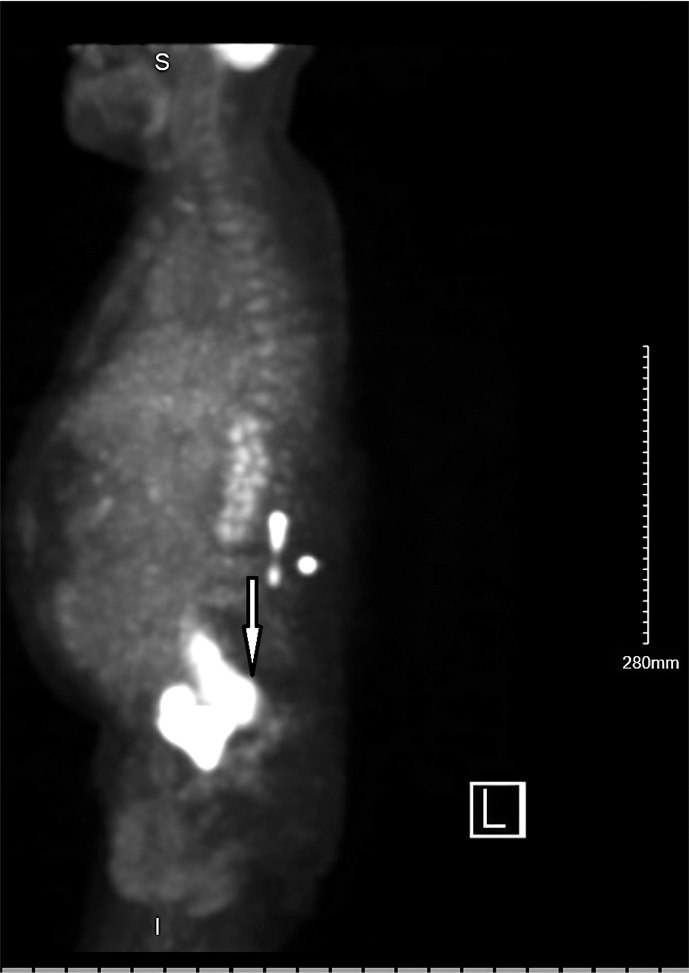

Case presentation: Here, we present a case of a male with liver disease with portal hypertension, a previous history of cancer, and prior surgery with an artificial urinary sphincter placement who developed acute recurrent ascites and rapidly progressing acute kidney failure requiring dialysis. Extensive workup revealed that the kidney failure was caused by SBR, resulting in urinary ascites. The bladder rupture was treated by surgery, leading to complete resolution of the patient's symptoms.